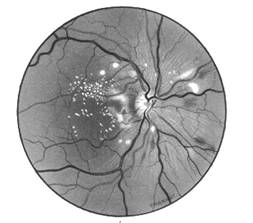

Din punct de vedere oftalmoscopic aspectul este destul de caracteristic, prezenta microanevrismelor cu aspect punctiform, rosii, rotunde si bine delimitate, fiind patognomonica pentru retinopatia diabetica (Fig. 17.6).

Fig. 17.6 - Microanevrisme, hemoragii striate si exsudate dure

in retinopatia diabetica neproliferativa